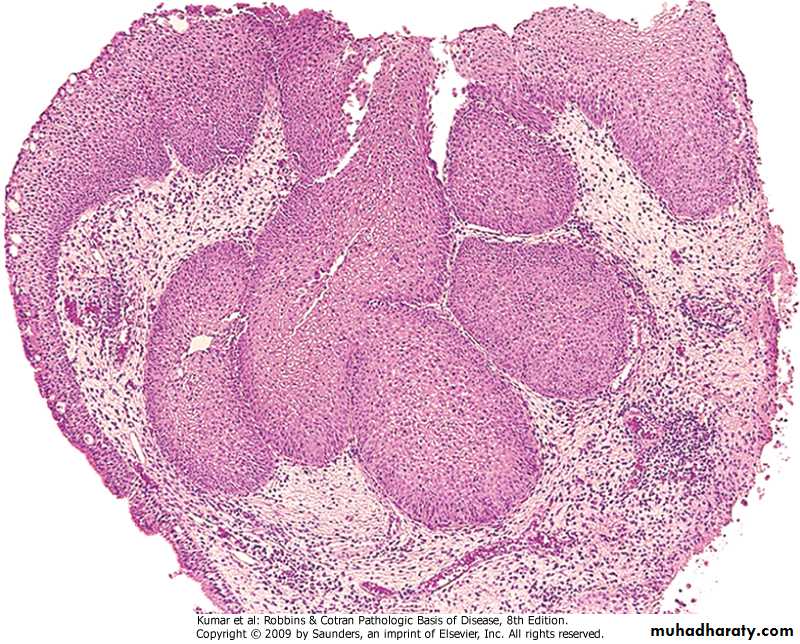

2. Lymphatic spread: To the hilar trachiobronchial , mediastinal supraclavicular lymph node leading to enlargement of the lymph node ( lymphadeno pathy)Spread of bronchogenic carcinoma (cont)